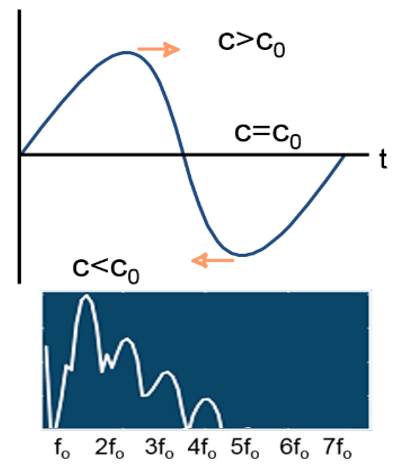

Non-Linear Propagation

Linear and nonlinear propagation are terms used to describe how soft tissues respond as the ultrasound wave propagates.

When the acoustic pressure of the ultrasound wave in soft tissue is small, the tissue behaves in a linear fashion, which means that the tissue expansion (rarefaction) and compression propagate at the same speed.

Nonlinear propagation occurs when high-pressure ultrasound waves travel through a compressible medium and the transmitted ultrasound pulse makes less compression than rarefaction.

- Propagation speed increases with density (pressure)

- The wave moves faster when the pressure is higher (peaks) and slower where it is lower (troughts)

- Any change from a perfect sinusoid creates harmonics

- The higher the amplitude, the more the effect

Principle

Harmonic frequencies are integer multiples of the fundamental frequency (for example if the fundamental frequency is f0, the harmonics have frequencies of 2f0, 3f0, and so on). The amplitudes of the harmonic waves are almost always lower than those of the fundamental frequency waves.

As we mentioned previously, the transmitted pulse consists of a range of frequencies centered around f0. In a linear medium, the echo pulse frequency is the same as the fundamental frequency but has lower energy, whereas the nonlinear medium results in harmonic waves of higher frequency and lower energy as shown in this figure. It is important to note that the majority of clinical US systems use second harmonic (ie, 2f0) echoes for THI image formation.